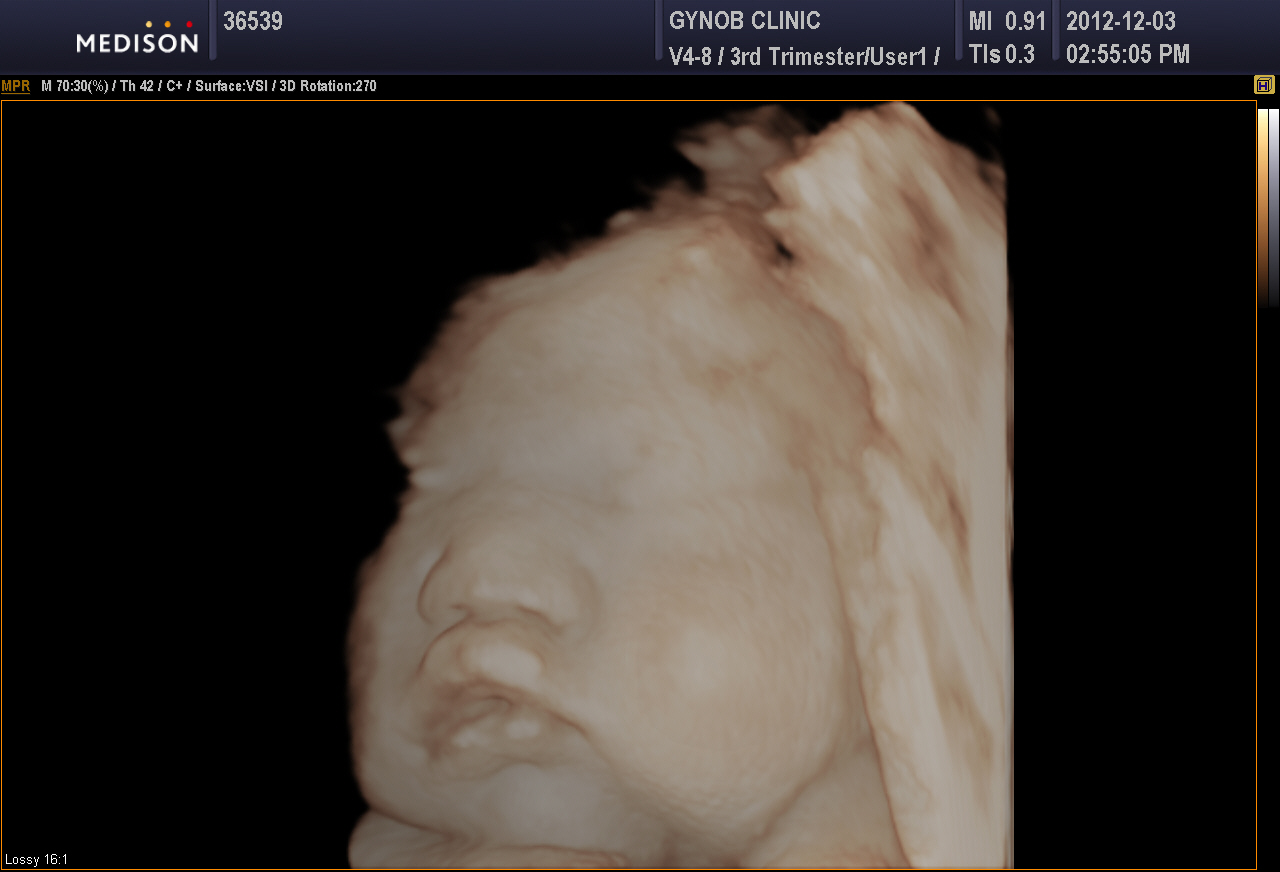

제목: 정O주 / 손O갑 님 초음파 사진 [프린트]

제목: 정O주 / 손O갑 님 초음파 사진

출산 날짜: 2012년 12월 26일 오전 5시 58분

아기 체중: 3.52kg

아기 성별: 여

초음파 사진

날짜: 2012년 12월 3일